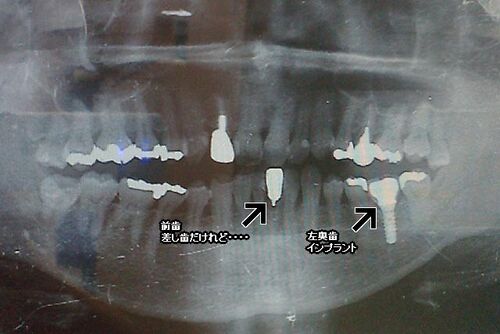

実は最近、2回ほど歯医者に通っていました。 前歯の1本が差し歯なのですが、はるか昔に硬いものを食べたら『バキッ』と嫌な音がして、ちょっとグラグラ。そのまま放置していたのですが、ここ最近、そのグ~ラグラが許容できないほどになり、かつ硬いものを噛…